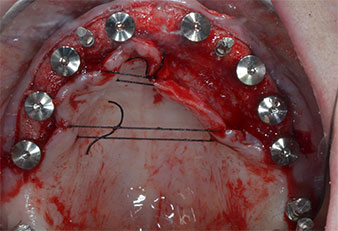

Pose d'implants

Fig. 1 : Vue préopératoire de la crête maxillaire, où les positions implantaires ont été marquées à l'aide d’un gabarit chirurgical en plastique. Compte tenu de la faible hauteur de la crête, des implants postérieurs très courts sont planifiés.